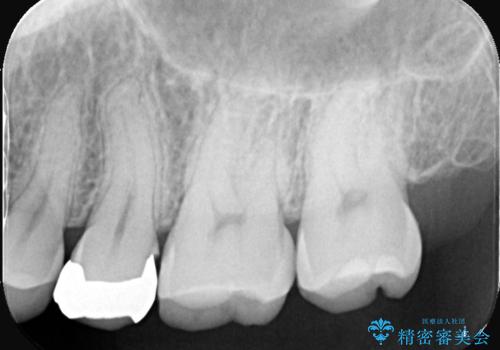

- 銀歯をやり替えたいとのことでした。残っている歯の量や長期的な予後をふまえ、患者様との相談の結果、被せ物での修復となりました。

メタルインレーを除去し、その下にあったう蝕を除去したうえで、CRにて築造を行い形成しました。印象時は圧排し、シリコンにて精密に行っています。